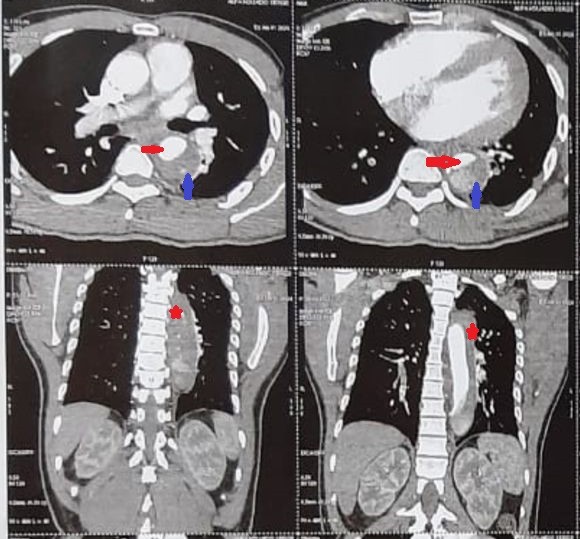

Figure 1: Angioscanner Thoracique en coupe axiale montrant l’aorte thoracique descendante disséquée avec le vrai chenal( flèche rouge) et le faux chenal non circulant(flèche bleu). Coupes frontales montrant l’aorte thoracique descendante disséquée (étoiles rouges).